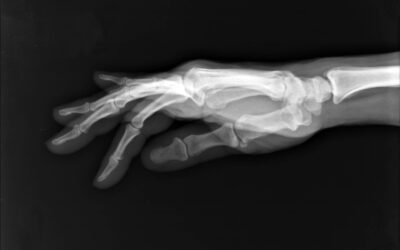

A fall on an outstretched hand—often called a FOOSH injury—is one of the most common ways people injure their wrist and hand. It can happen during sports, slips on wet surfaces, cycling accidents,...